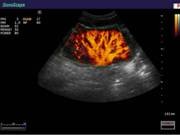

Компания SonoScape уделила особое внимание допплеровским режимам и является экспертом в своем классе, что позволяет с легкостью, но в то же время с уникальной точностью проводить исследования с постановкой наиболее точного диагноза.

Ультразвуковые исследования, доплеровское сканирование сосудов в Центре современных медицинских технологий «АКВА МЕД МАРИН» выполняется при помощи первого и единственного аппарата в Керчи SonoScape S40Exp (экспертного класса, который оснащен множеством новейших функций, многократно улучшающих качество и информативность УЗИ-исследования).